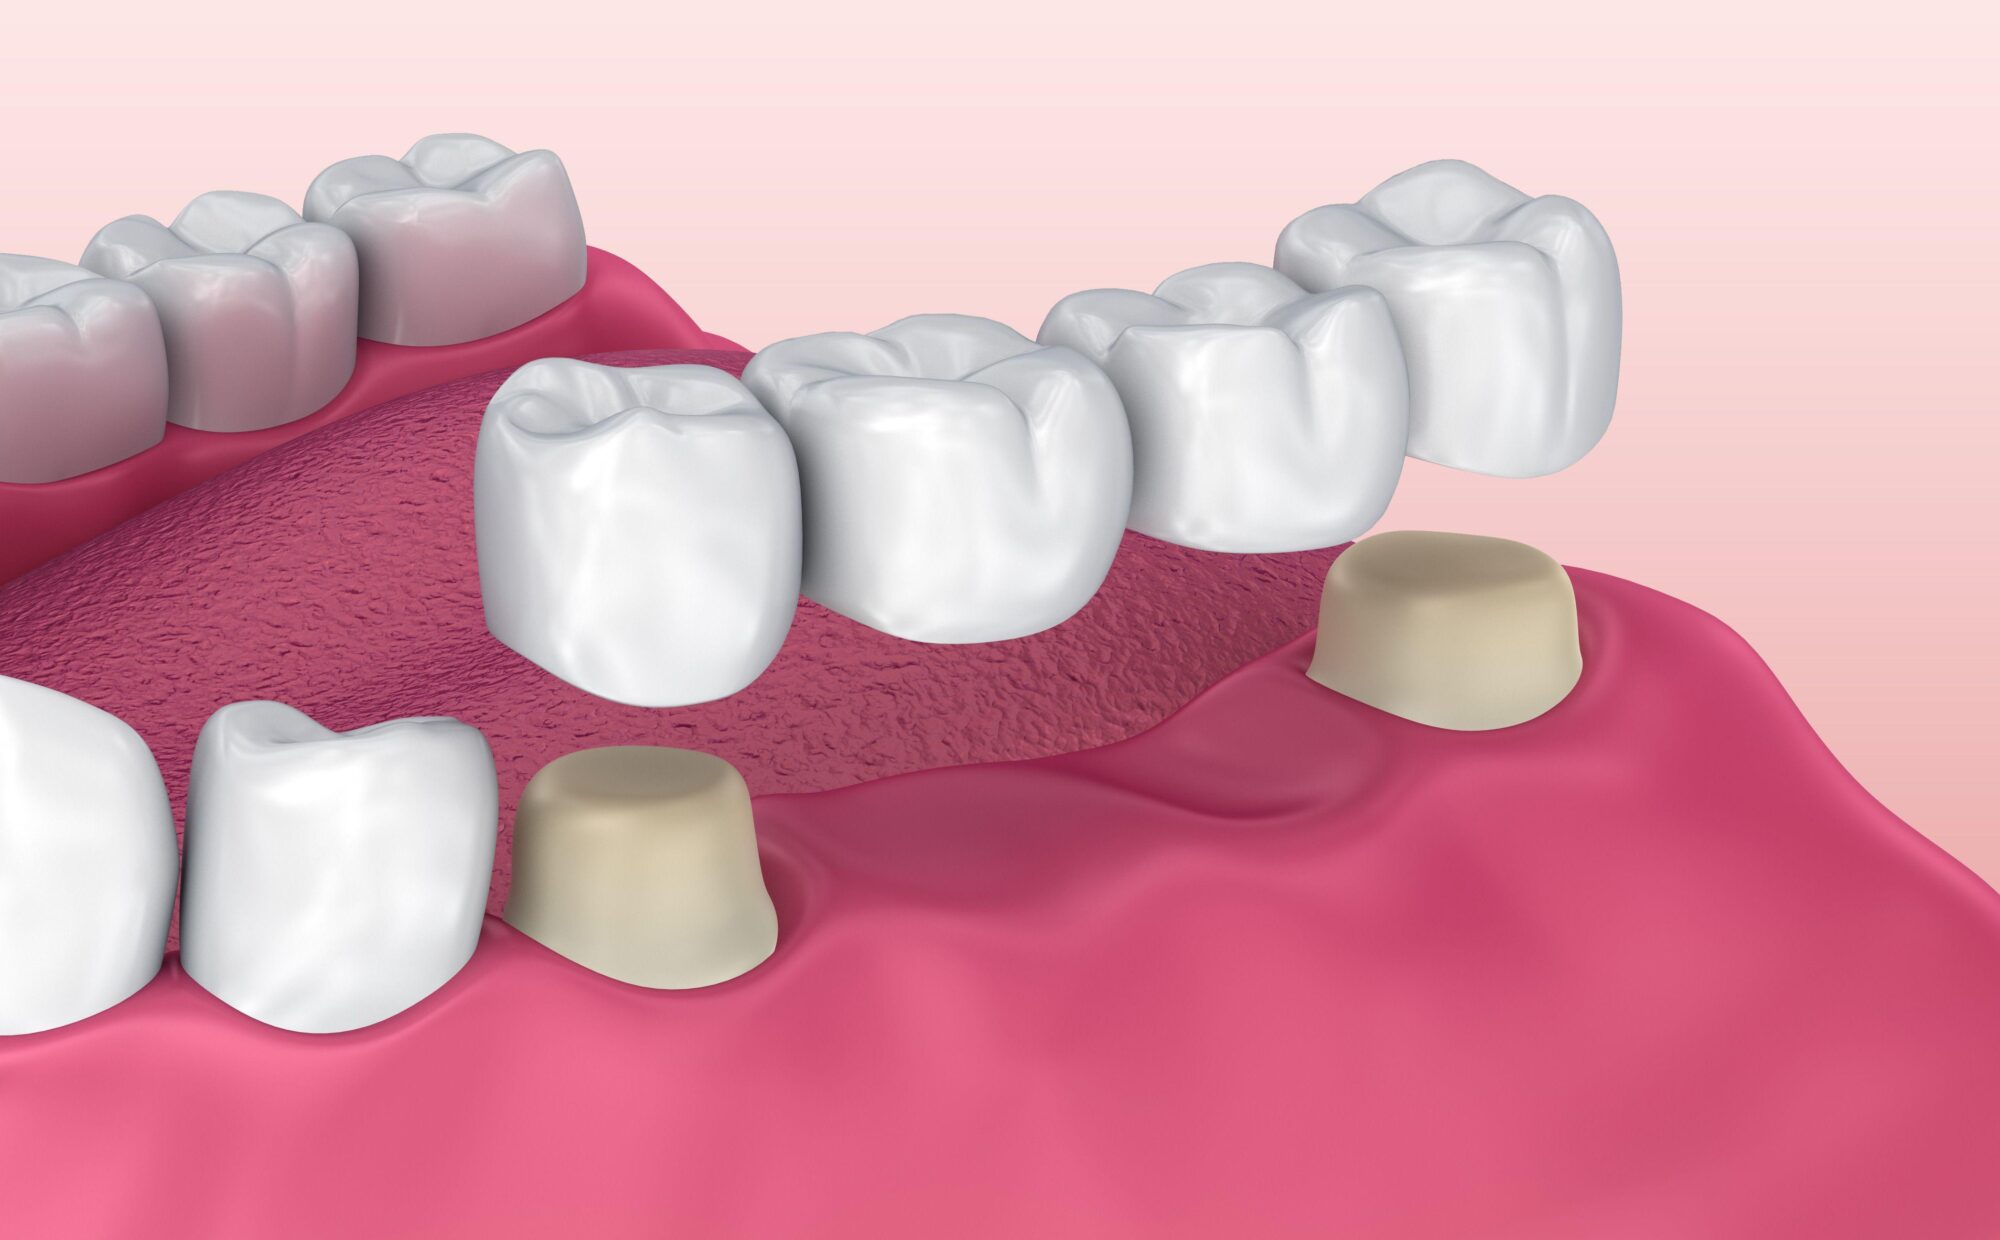

Bridges

Les bridges dentaires, des prothèses qui se fixent sur les dents voisines à une ou plusieurs dents absentes, à la manière d’un pont. Leur indication est bien plus limitée depuis l’essor de l’implantologie.

Lorsque la racine de la dent est abîmée, la pose d’une couronne ou d’un bridge est précédée par la pose d’un implant dentaire, une vis en titane implantée dans l’os de la mâchoire, en remplacement de la racine dentaire concernée. Si l’état de la gencive ou de l’os ne permettent pas de supporter l’implant, une greffe vous sera proposée en amont de cette intervention.